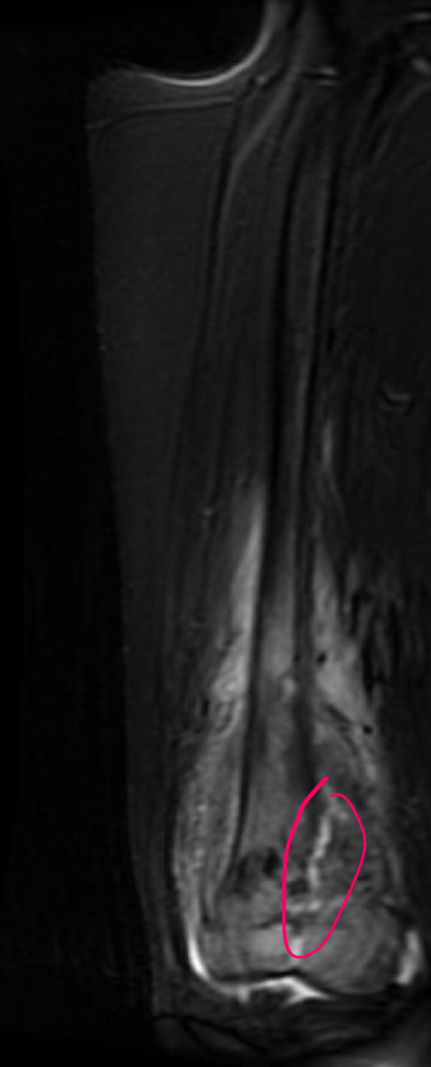

Q se ve y para q sirve rm

estadificacion

Determinar conservacion de extremidad

Extension intraosea y a tejido blando

Contraste

14

Otro ejemplos de osteosarcoma